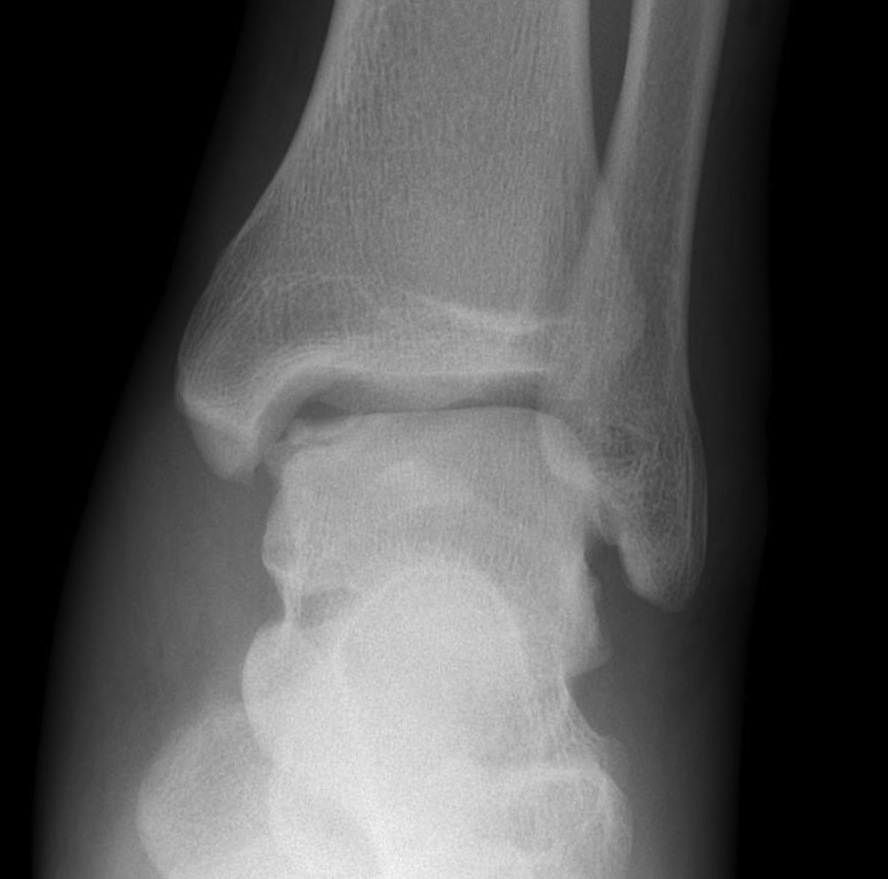

Xray

Stage II medial osteochondral fragments

Stage III medial osteochondral fragments

Stage IV anterolateral osteochondral fragment